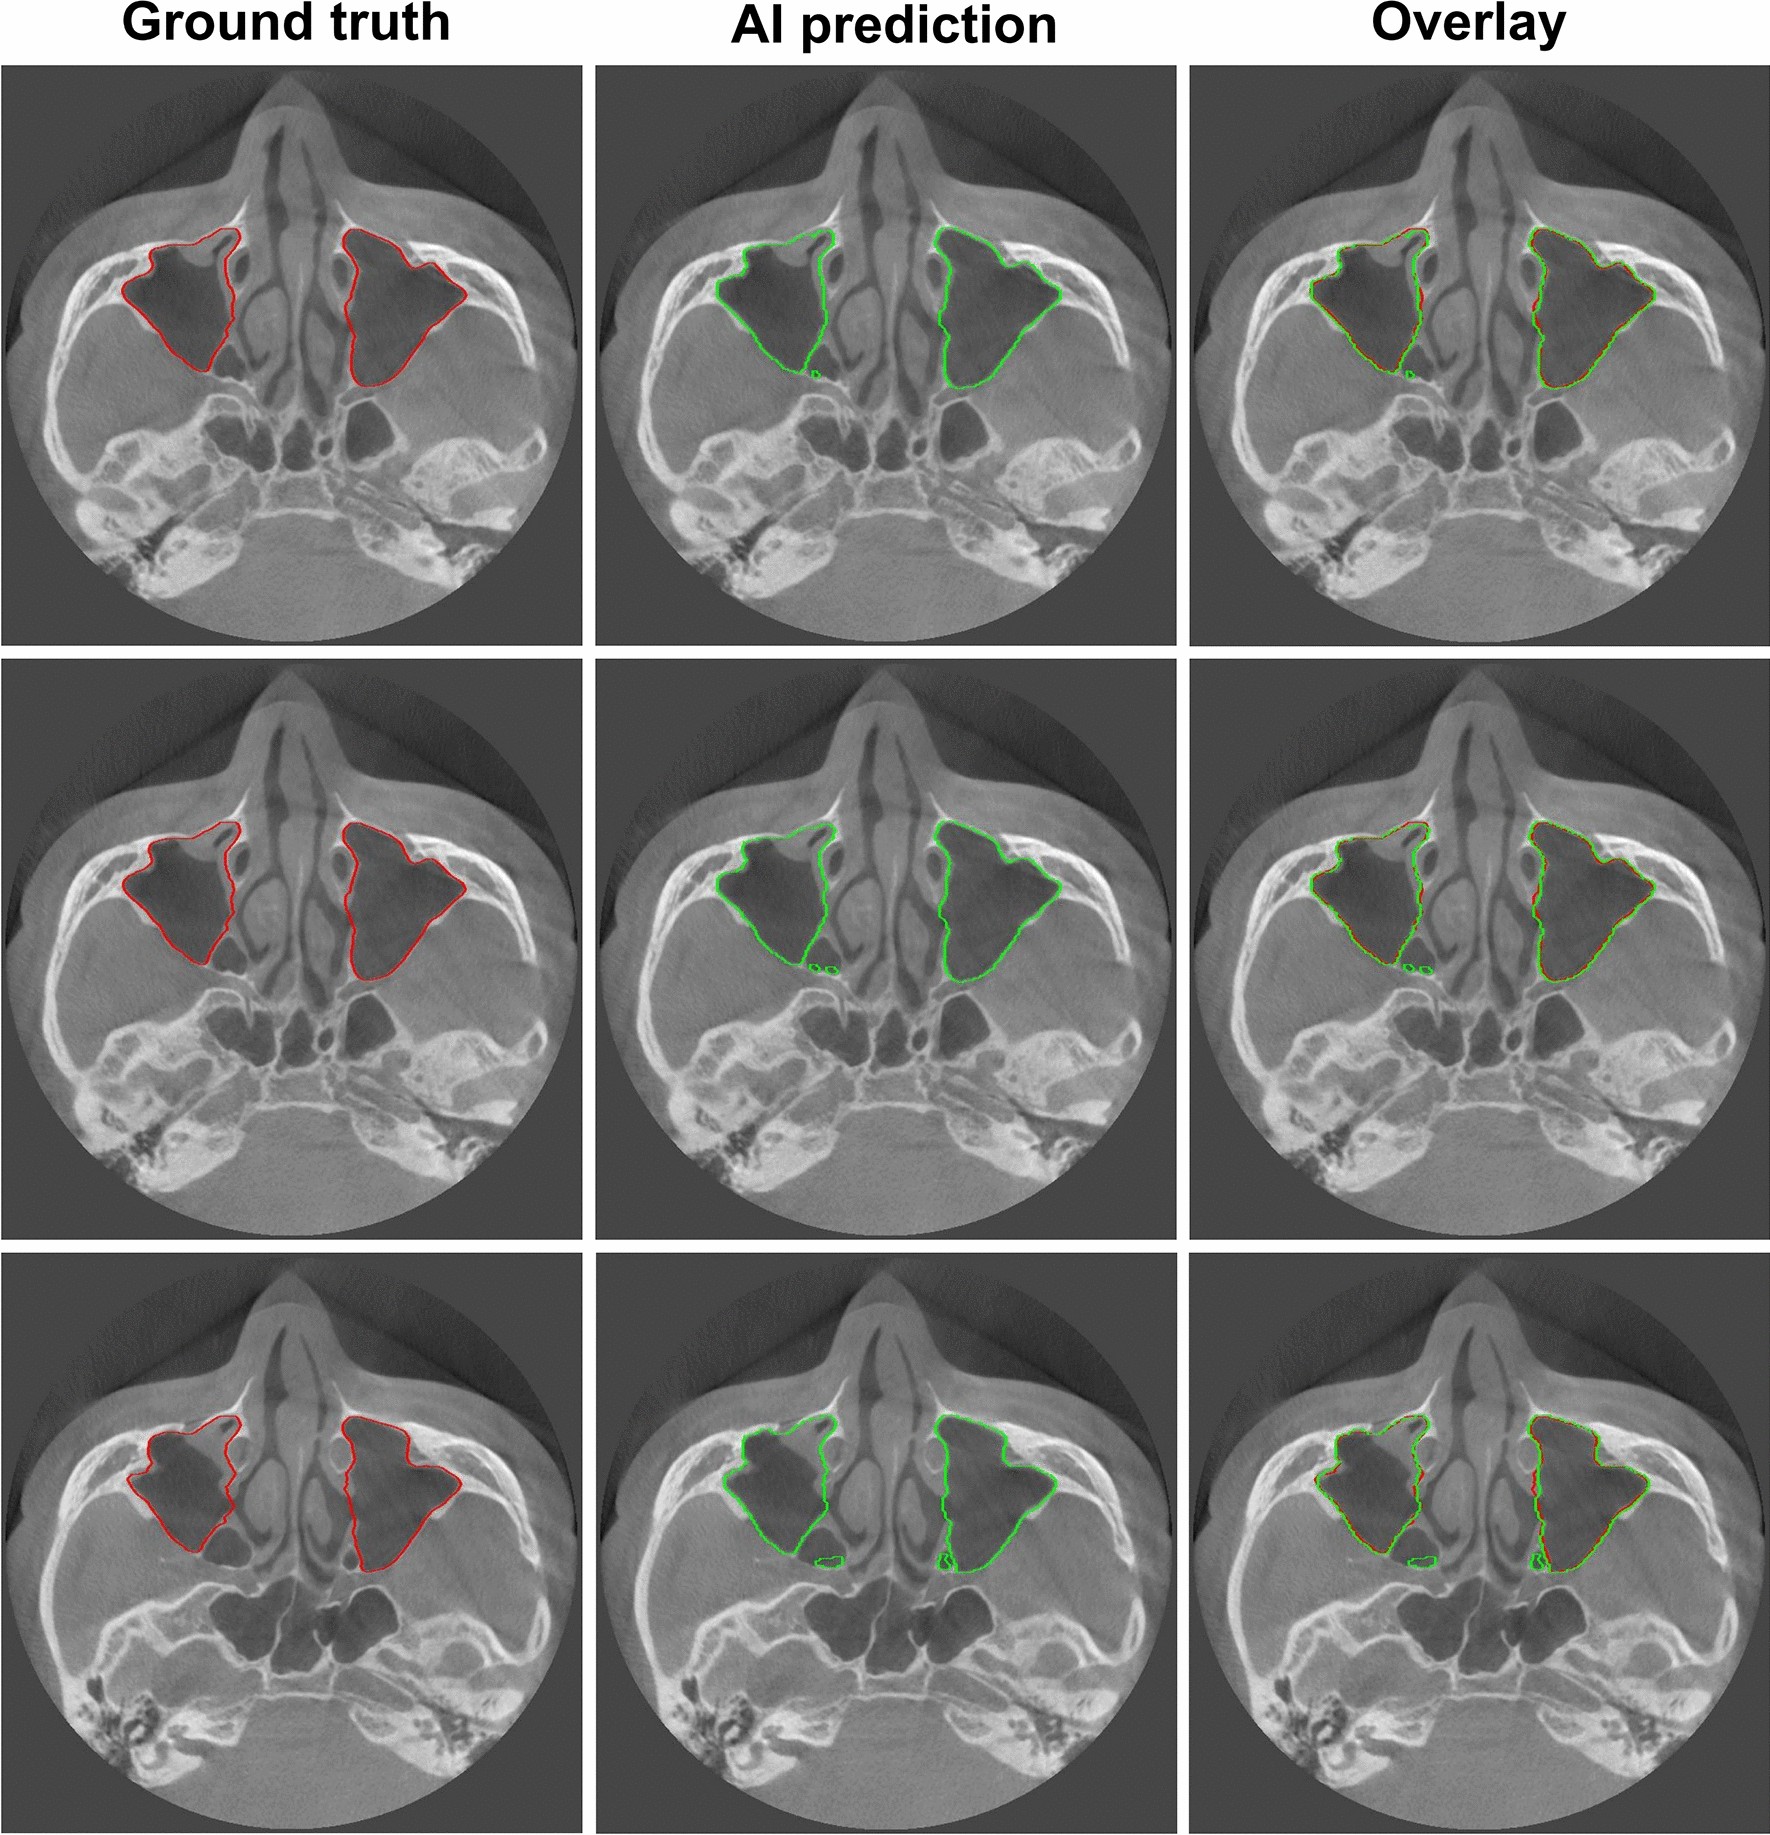

Figure 6

Worst results of maxillary sinus segmentation. The mispredicted part in the posterior part of the maxillary sinus is the ethmoid sinus. Red: the edges of the ground truth image; green: the edges of the artificial intelligence (AI) prediction image.